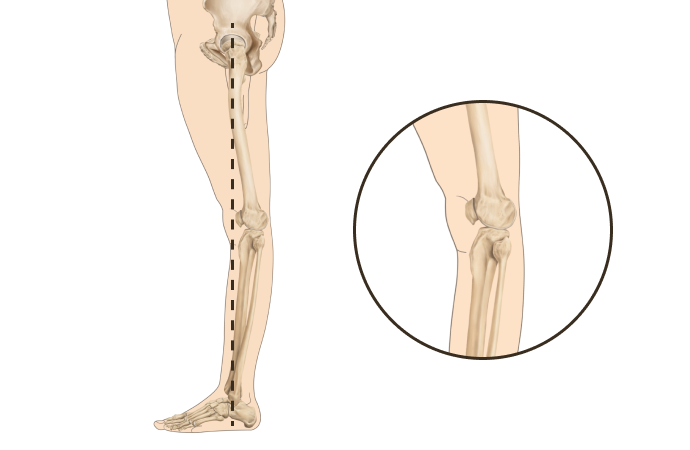

▲ O자 다리

▲ 정상 다리

휜다리의 대표적 유형 2가지

O다리

• 무릎이 외측으로 벌어지면서 다리 축이 변형됨

• 체중부하가 다리 안쪽(내측)에 집중되어 내측 관절의 압력증가로

무릎관절의 퇴행성 변화와 통증을 초래

• 허벅지 안쪽 근육이나 엉덩이 근육이 약화되면 무릎 안정성이 떨어져 내반슬이 악화

X다리

• 무릎이 안쪽으로 모이면서 다리 축이 변형됨

• 체중 부하가 다리 바깥쪽에 집중되어 외측 관절의 압력증가로

무릎 통증, 불안정성, 관절 손상을 유발할 수 있음

• 허벅지 바깥쪽 근육이 과도하게 발달하고 안쪽 근육이 약화되면 외반슬이 진행

측면부에서 휜다리의 정렬에 따라

정상

신전형 (Back knee)

무릎 정상패턴과 신전패턴 2가지

휜다리는 단순히 무릎 사이 간격이 벌어진 것이 아닙니다.

무릎 위의 대퇴골과 아래의 정강이뼈가 회전하면서 무릎까지 뒤로 빠지기 때문에 다리사이 간격이 넓어지는 겁니다.